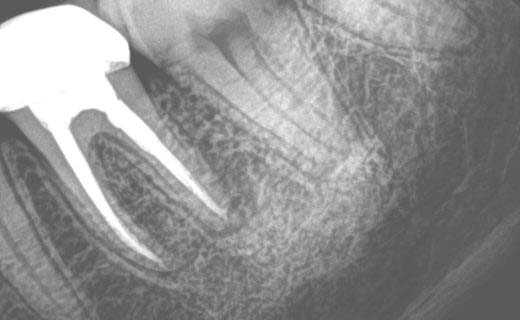

Periapical X-Ray (Dental PA X-Ray)

One of the most common types of dental X-Rays is the periapical X-Ray, often referred to as PA X-Rays or just PA. This type captures the entire tooth from the crown to the root and surrounding bone. Periapical X-Rays are great for detecting issues such as abscesses (infections at the root tip), bone loss due to periodontal disease, impacted teeth and abnormalities in the root structure. We use them to monitor the progress of root canal treatments or to check the healing after tooth extractions.

Cone Beam Computed Tomography (Dental CBCT scan) is a more advanced type of dental imaging that gives us a 3D view of the entire head. Unlike conventional X-Rays that produce 2D images, CBCT scans give us a much more detailed and accurate representation of the dental structures. This advanced technology is used for complex cases such as in case of full mouth reconstruction with dental implants, and sometimes surgical planning for impacted teeth extractions and evaluation of TMJ disorders. Digital subtraction radiography of CT scan allows us to detect vertical fracture. However, CBCT scans involve a higher dose of radiation than conventional digital dental X-Rays and are used when the benefits outweigh the risks.

Abscesses and Infections: Infections at the root of a tooth or in the surrounding bone can be seen on dental digital X-Rays as dark areas where pus is accumulating. Early detection and treatment of abscesses is key to preventing the spread of infection.